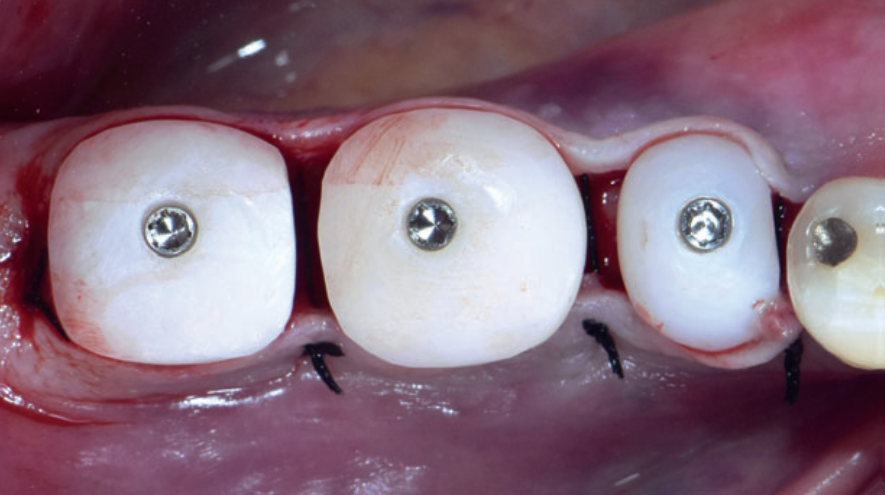

Ao serem instalados, os implantes que atingem um torque de inserção ≥ 32 Ncm podem ser imediatamente carregados com coroas unitárias de transição não oclusivas. Abaixo deste torque, ou em situações onde não desejamos correr riscos, em vez de uma coroa de transição, instala-se um cicatrizador personalizado contendo um perfil transmucoso com as mesmas características que a coroa provisória teria. Os objetivos dos cicatrizadores customizados nos casos de instalação do implante imediatamente após a exodontia são: selar o sítio cirúrgico respeitando o perfil do alvéolo de extração, estabilizar o coágulo sanguíneo e favorecer a regeneração óssea com o material substituto, evitar o colapso de tecidos moles durante o período de cicatrização e desenvolver um perfil de emergência protético ideal para a futura coroa sobre implante, baseado na anatomia do dente natural extraído, sem receber carga oclusiva.

Nos casos de instalação de implantes em regiões edêntulas, também é possível empregar cicatrizadores personalizados, desenvolvendo um perfil de emergência protético ideal para a futura coroa sobre implante, baseado na anatomia do dente natural ausente. Os dois procedimentos restabelecerão o perfil de emergência original do paciente durante a fase de cicatrização/osseointegração dos implantes, devolvendo a harmonia dentogengival, com a recuperação das papilas interdentais e a reconstituição do arco gengival côncavo, com altura adequada da margem em relação aos dentes adjacentes.

Quando corretamente indicados e executados, os cicatrizadores personalizados proporcionam bons resultados estéticos, biológicos e funcionais. A criação/manutenção de um perfil de emergência anatomicamente correto é um dos aspectos mais importantes para fornecer resultados estéticos e funcionais agradáveis às próteses implantossuportadas, tanto no setor anterior quanto no setor posterior.